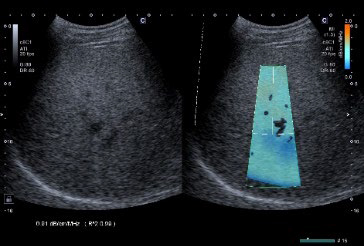

●Attenuation Imaging(ATI)

ATIは,腹部検査用の標準的なプローブを用いて超音波周波数依存減衰を測定することのできる臨床アプリケーション。超音波減衰法検査としてATIは,指定された領域の減衰係数をカラー表示することができ,NASH(nonalcoholic steatohepatitis:非アルコール性脂肪肝炎)診断への有用性が期待されている[1]。Aplio flexのATIは減衰係数の経時的変化をグラフで表現できる。(Aplio flexのみ搭載可能なオプション)

Attenuation Imagingによる検査画面